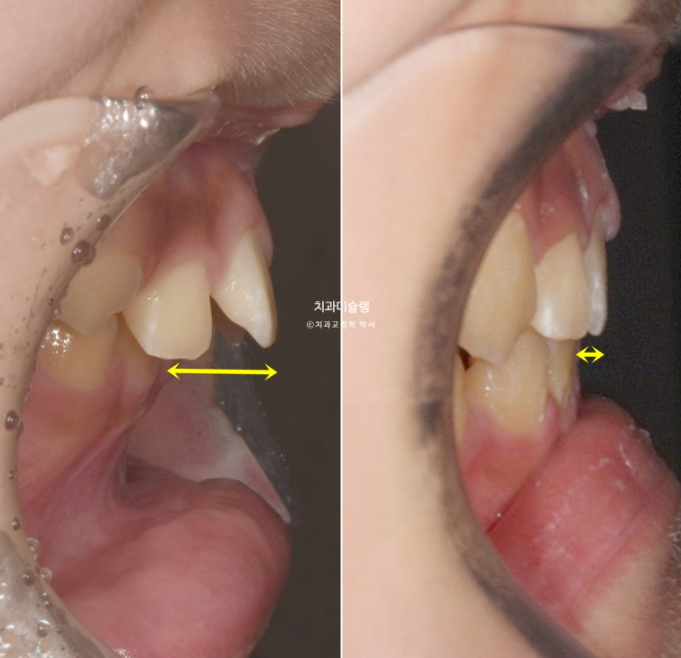

파란화살표 자리에 있어야할 작은어금니가 선천적 결손 상태입니다.

이런 경우 계승영구치가 없어 오래도록 남아있게될 잔존유치를 최대한 보존해서 쓰는 방법으로 치료를 합니다.

잔존유치를 오래 보존해서 사용하기로 했다면 교정 치료 중 불필요한 치아이동에 의해 잔존유치치근이 녹아 짧아지지 않도록 각별히 신경써야 합니다.

유치는 교정력을 받았을때 영구치와 다르게 잘 움직이지 않을 뿐더러, 안그래도 영구치에 비해 뿌리가 약한 상태이니 치근흡수라도 나타나면 발치해야 하는 애매한 상황이 생깁니다.

중심선이 여전히 틀어져 있는 이유는

파란 화살표의 잔존유치가 정상영구치보다 사이즈가 1.5배 크기 때문입니다.

하지만 어금니 교합은 1급 교합관계를 달성했고

파란 화살표 잔존유치는 초진에 비하여 치근흡수 없이 잘 보존되었습니다.

다른 영구치들에 치근흡수는 없고 치근평행도는 좋습니다.

선천적 결손이라고 해도 치료를 잘 해주면 별 문제 없이 교정 마무리가 가능합니다.